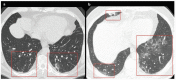

A new type of coronavirus (2019-nCoV) is rapidly spreading worldwide and causes pneumonia, respiratory distress, thromboembolic events, and death. Chest computed tomography (CT) plays an essential role in the diagnosis of viral pneumonia, monitoring disease progression, determination of disease severity, and evaluating therapeutic efficacy. Chest CT can show important clues of 2019-nCoV disease (also known as COVID-19) in patients with an appropriate clinic. Prompt diagnosis of COVID-19 is essential to prevent disease transmission and provides close clinical observation of patients with clinically severe disease. Therefore, radiologists and clinicians should be familiar with the CT imaging findings of COVID-19 pneumonia. Herein, we aimed to review the imaging findings of COVID-19 pneumonia and examine the critical points to be considered for imaging in cases with COVID-19 suspicion.